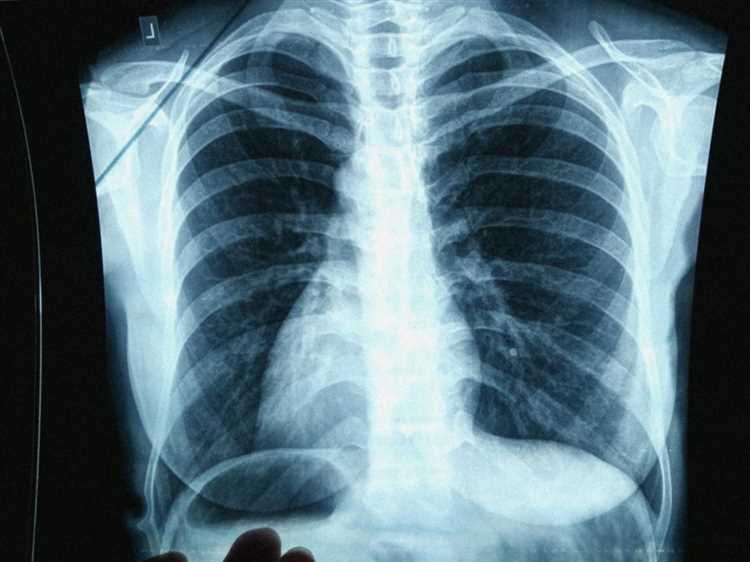

После записи пациент направляется в флюорографический кабинет, где производится обследование. Процесс занимает несколько минут, а результат обрабатывается с использованием цифровых технологий, что снижает радиационную нагрузку и повышает точность диагностики.

Результаты флюорографии обычно становятся доступными через 1-2 рабочих дня. Если патологий не выявлено, работник получает заключение, которое фиксируется в медицинской карте. В случае обнаружения отклонений от нормы назначается дополнительное обследование или консультация специалиста.